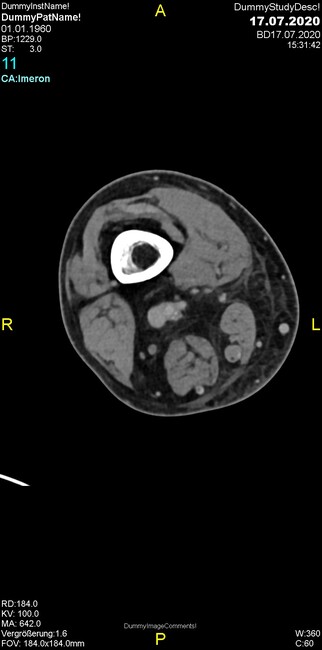

Um welche Modalitäten handelt es sich?

- Röntgen p.a. und lateral, CT coronar Knochenfenster, CT axial Weichgewebsfenster

Was trifft auf den Befund zu?

- Der Befund beschränkt sich auf den Knochen.

- Es besteht hochakuter Handlungsbedarf.

- Der Befund ist tendenziell benigne.

- Der Befund ist tendenziell maligne.

- Der Befund weist einen Zusammenhang zum Patientenalter auf.

Was kommt differentialdiagnostisch in Frage?

- Kompartmentsyndrom

- Osteomyelitis mit Weichgewebsanteil

- Metastase mit pathologischer Fraktur

- Rheumatoide Athritis

- Posttraumatische Verletzung